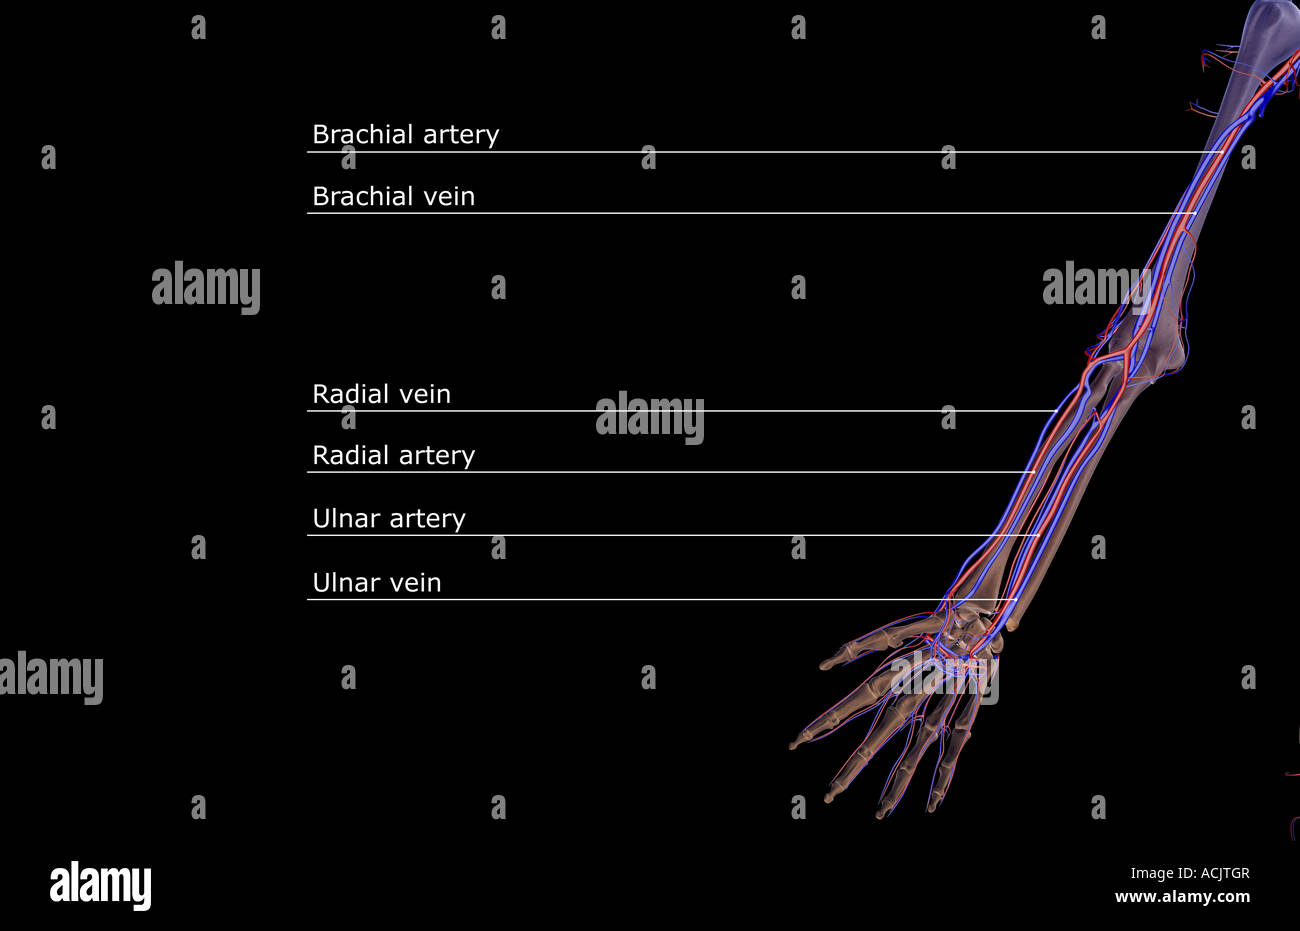

The blood supply of the upper limb Stock Photohttps://www.alamy.com/image-license-details/?v=1https://www.alamy.com/stock-photo-the-blood-supply-of-the-upper-limb-13173190.html

The blood supply of the upper limb Stock Photohttps://www.alamy.com/image-license-details/?v=1https://www.alamy.com/stock-photo-the-blood-supply-of-the-upper-limb-13173190.htmlRFACJTGR–The blood supply of the upper limb